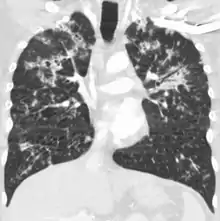

A case of miliary tuberculosis in an 82-year-old woman:

- CT, 16 days after onset, showing extensive pulmonary parenchymal involvement consisting of irregular septal thickenings with ground-glass areas and centrilobular nodules with a peri-lymphatic distribution